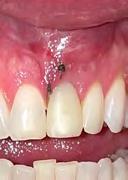

1. Pre-operative image showing a fractured, endodontically treated tooth #9.